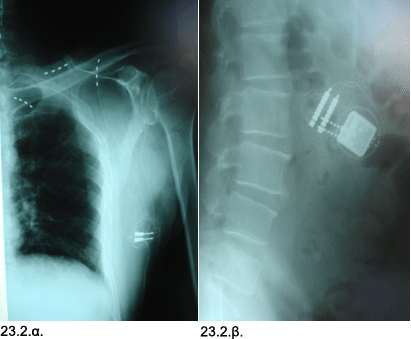

Εικόνες 23.2.α. & 23.2.β. Απλές ακτινογραφίες δείχνουν την διαδερμική τοποθέτηση των κυλινδρικών ηλεκτροδίων προσωρινής δοκιμαστικής διέγερσης περιφερικού νευρικού πεδίου (23.2.α.) και την ελάχιστα επεμβατική τοποθέτηση διαχρονικών κυλινδρικών ηλεκτροδίων για μακροχρόνιο διέγερση περιφερικού νευρικού πεδίου, μέσω κατάλληλου νευροδιεγέρτη (23.2.β.).

Ιστορικό: Άνδρας 57 ετών, με ιστορικό αυχενικής μυελοπάθειας και έντονου χρόνιου πόνου στην υποκλείδιο χώρα, στο άνω άκρο, στον ώμο και στην ωμοπλάτη δεξιά κατά τα τελευταία πέντε έτη. Ο ασθενής ανέφερε ότι στη προσπάθεια τερματισμού του πόνου είχε επίσης υποβληθεί σε πρόσθια αυχενική δισκεκτομή, η οποία όμως δεν συνέβαλλε στο να μειωθεί ο πόνος, παρά το γεγονός ότι η επέμβαση είχε πραγματοποιηθεί με σωστό τρόπο και αλλά προοδευτικά έγινε εντονότερος. Επίσης, η λήψη πολλών φαρμάκων, κατόπιν οδηγιών που εδόθησαν σε ιατρεία πόνου, δεν προσέφεραν σημαντική ωφέλεια.

Αντιμετώπιση: Ο ασθενής υποβλήθηκε σε δοκιμαστική ηλεκτρική διέγερση περιφερικού νευρικού πεδίου με κυλινδρικά ηλεκτρόδια και ο πόνος μειώθηκε από τον βαθμό 8/10 στο βαθμό 4/10 στην στην Κλίμακα Πόνου VAS (Visual Analog Scale). Μετά την επιτυχή δοκιμαστική διέγερση, ο ασθενής υποβλήθηκε σε ελάχιστα επεμβατική τοποθέτηση χρονίων ηλεκτροδίων ηλεκτρικής διέγερσης περιφερικού νευρικού πεδίου, η οποία διατήρησε αυτό το αποτέλεσμα στην αρχική φάση, και μετά μία περίοδο επιτυχούς προγραμματισμού του συστήματος διέγερσης, η μέθοδος προσέφερε προοδευτικά ακόμη μεγαλύτερη αποτελεσματικότητα, μειώνοντας τον πόνο από τον βαθμό 8/10 στον βαθμό 3/10 στην Κλίμακα Πόνου VAS (Visual Analog Scale) και ακόμη μείωσε την ανάγκη λήψης αναλγητικών φαρμάκων. Το ικανοποιητικό αποτέλεσμα διατηρήθηκε για τέσσερα χρόνια, αλλά ο ασθενής υπέστη τροχαίο ατύχημα, κατά το οποίο συνέβη βλάβη του διεγέρτη, και μετά από μικρό χρονικό διάστημα, ο πόνος άρχισε προοδευτικά να επανέρχεται στην προτέρα ένταση. Έγινε αντικατάσταση του συστήματος διέγερσης με νέο, καλώς λειτουργούν, και αυτό επανέφερε την μεγάλη ωφέλεια στον έλεγχο του πόνου, αποτέλεσμα το οποίο έχει παραμείνει μέχρι σήμερα.